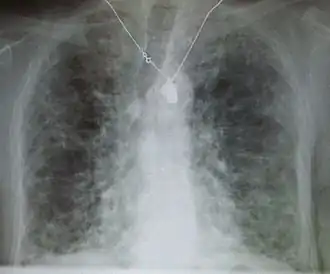

Pneumocystis pneumonia can present with interstitial lung disease, as seen in the reticular markings on this AP chest x-ray.

A chest X-ray demonstrating pulmonary fibrosis due to amiodarone

Diagnosis of ILD involves assessing the signs and symptoms as well as a detailed history investigating occupational exposures. ILD usually presents with dyspnea, worsening exercise intolerance and 30-50% of those with ILD have a chronic cough. On examination, velcro crackles, in which the crackles compare to the sound of velcro being unfastened, are common in ILD.[10] Pulmonary function tests usually show a restrictive defect with decreased diffusion capacity of carbon monoxide (DLCO) indicating reduced alveolar to blood capillary transport.[10] Pulmonary function testing is indicated for all people with ILD and the FVC loss and DLCO is prognostic, with an FVC loss of greater than 5% per year associated with a poor prognosis in fibrosis subtypes of ILD.[10]

A chest x-ray is 63% sensitive and 93% specific for ILD.[10] With advances in computed tomography, CT scans of the chest have supplanted lung biopsy as the preferred diagnostic test for ILD. A thoracic CT scan is 91% sensitive and 71% specific for ILD.[10] In higher income countries, less than 10% of people with ILD undergo a lung biopsy as part of the diagnostic evaluation.[16]